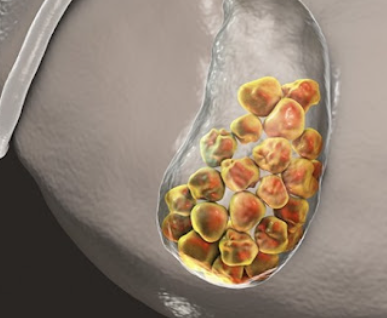

담석

담석은 담낭이나 담도 내에서 형성되는 고체 물질입니다. 대부분 담석은 콜레스테롤, 담즙산, 또는 양 세균성 담석으로 분류됩니다.

담석 종류

1. 콜레스테롤 담석

콜레스테롤이 담낭 내에서 과도하게 농축되어 콜레스테롤 결정이 형성되는 경우입니다. 콜레스테롤 담석은 주로 혈중 콜레스테롤 수치가 높은 사람들에게서 발생합니다.

2. 담즙산 담석

담즙산이 과도하게 농축되어 담낭 내에서 결정을 형성하는 경우입니다. 담즙산 담석은 일반적으로 담낭에서 담즙의 pH가 증가하여 발생할 수 있습니다.

3. 양 세균성 담석

담도 내에서 세균이 성장하여 담석을 형성하는 경우입니다. 이는 담도 내에 염증이나 감염이 있는 경우에 발생할 수 있습니다.

담석은 보통은 작고 작은 결정으로 시작해 담도를 차단할 수 있습니다. 이로 인해 복통, 구토, 설사 등의 증상이 발생할 수 있습니다. 일부 경우에는 담석이 담도를 차단하여 심각한 감염을 유발할 수도 있습니다.